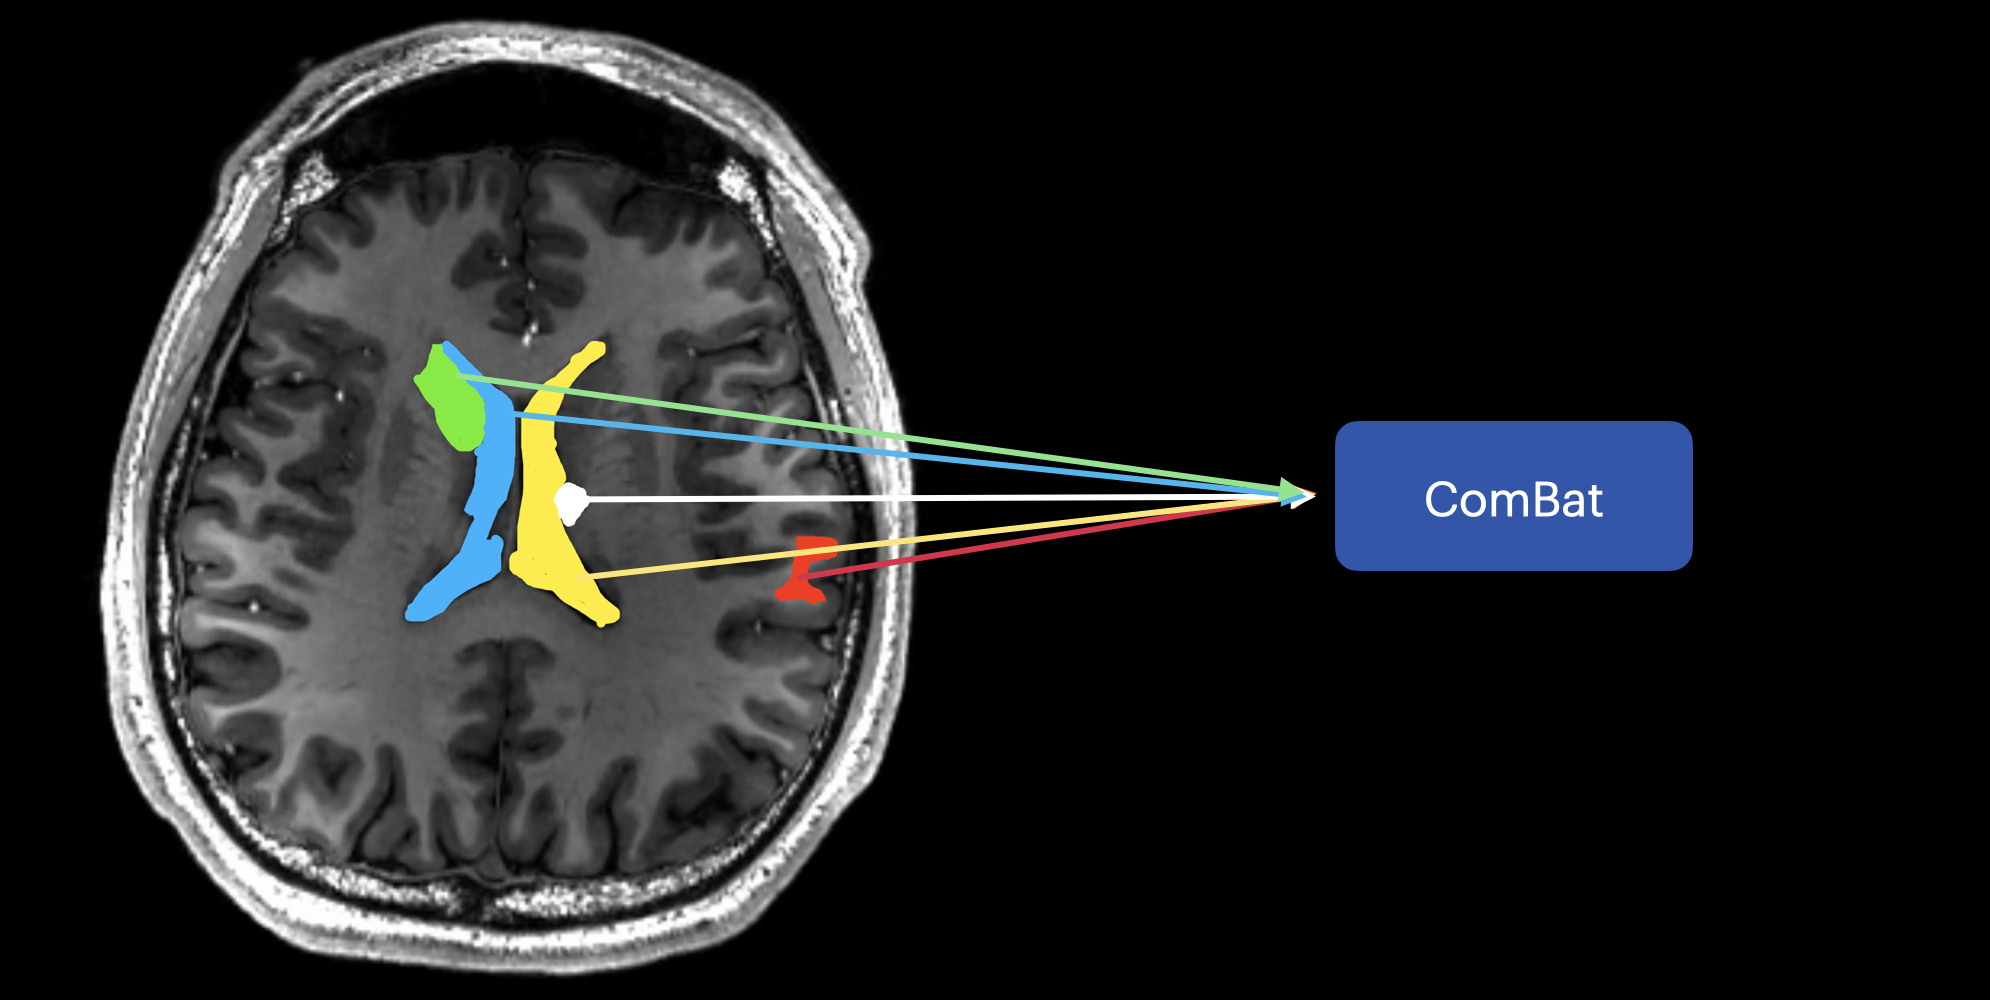

Figure 3: Some sample ROIs in the image are displayed in different colors.

However, ComBat considers brain regions (i.e. ROIs) separately, as shown in Figure 3, hence may not be able to remove site differences that are across regions.